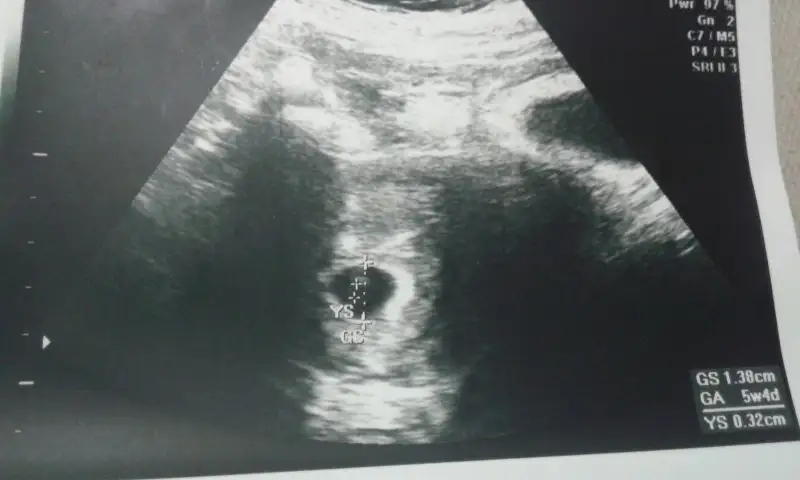

Kızlar ben bugün keseyi gördüm çok şükür yolk sac da var günüyle uyumlu dedi ama kalbini duymadan sağlıklı hamilelik diyemem dedi 10gün sonra gel dedi bende başka bi hastaneden cumartesi günü için randevu aldım doktor çok fazla bilgi vermedi çünkü sizde durumlar nasıl

Eklentiler

• 20161004_234420.webp

20161004_234420.webp

13,6 KB · Görüntüleme: 71